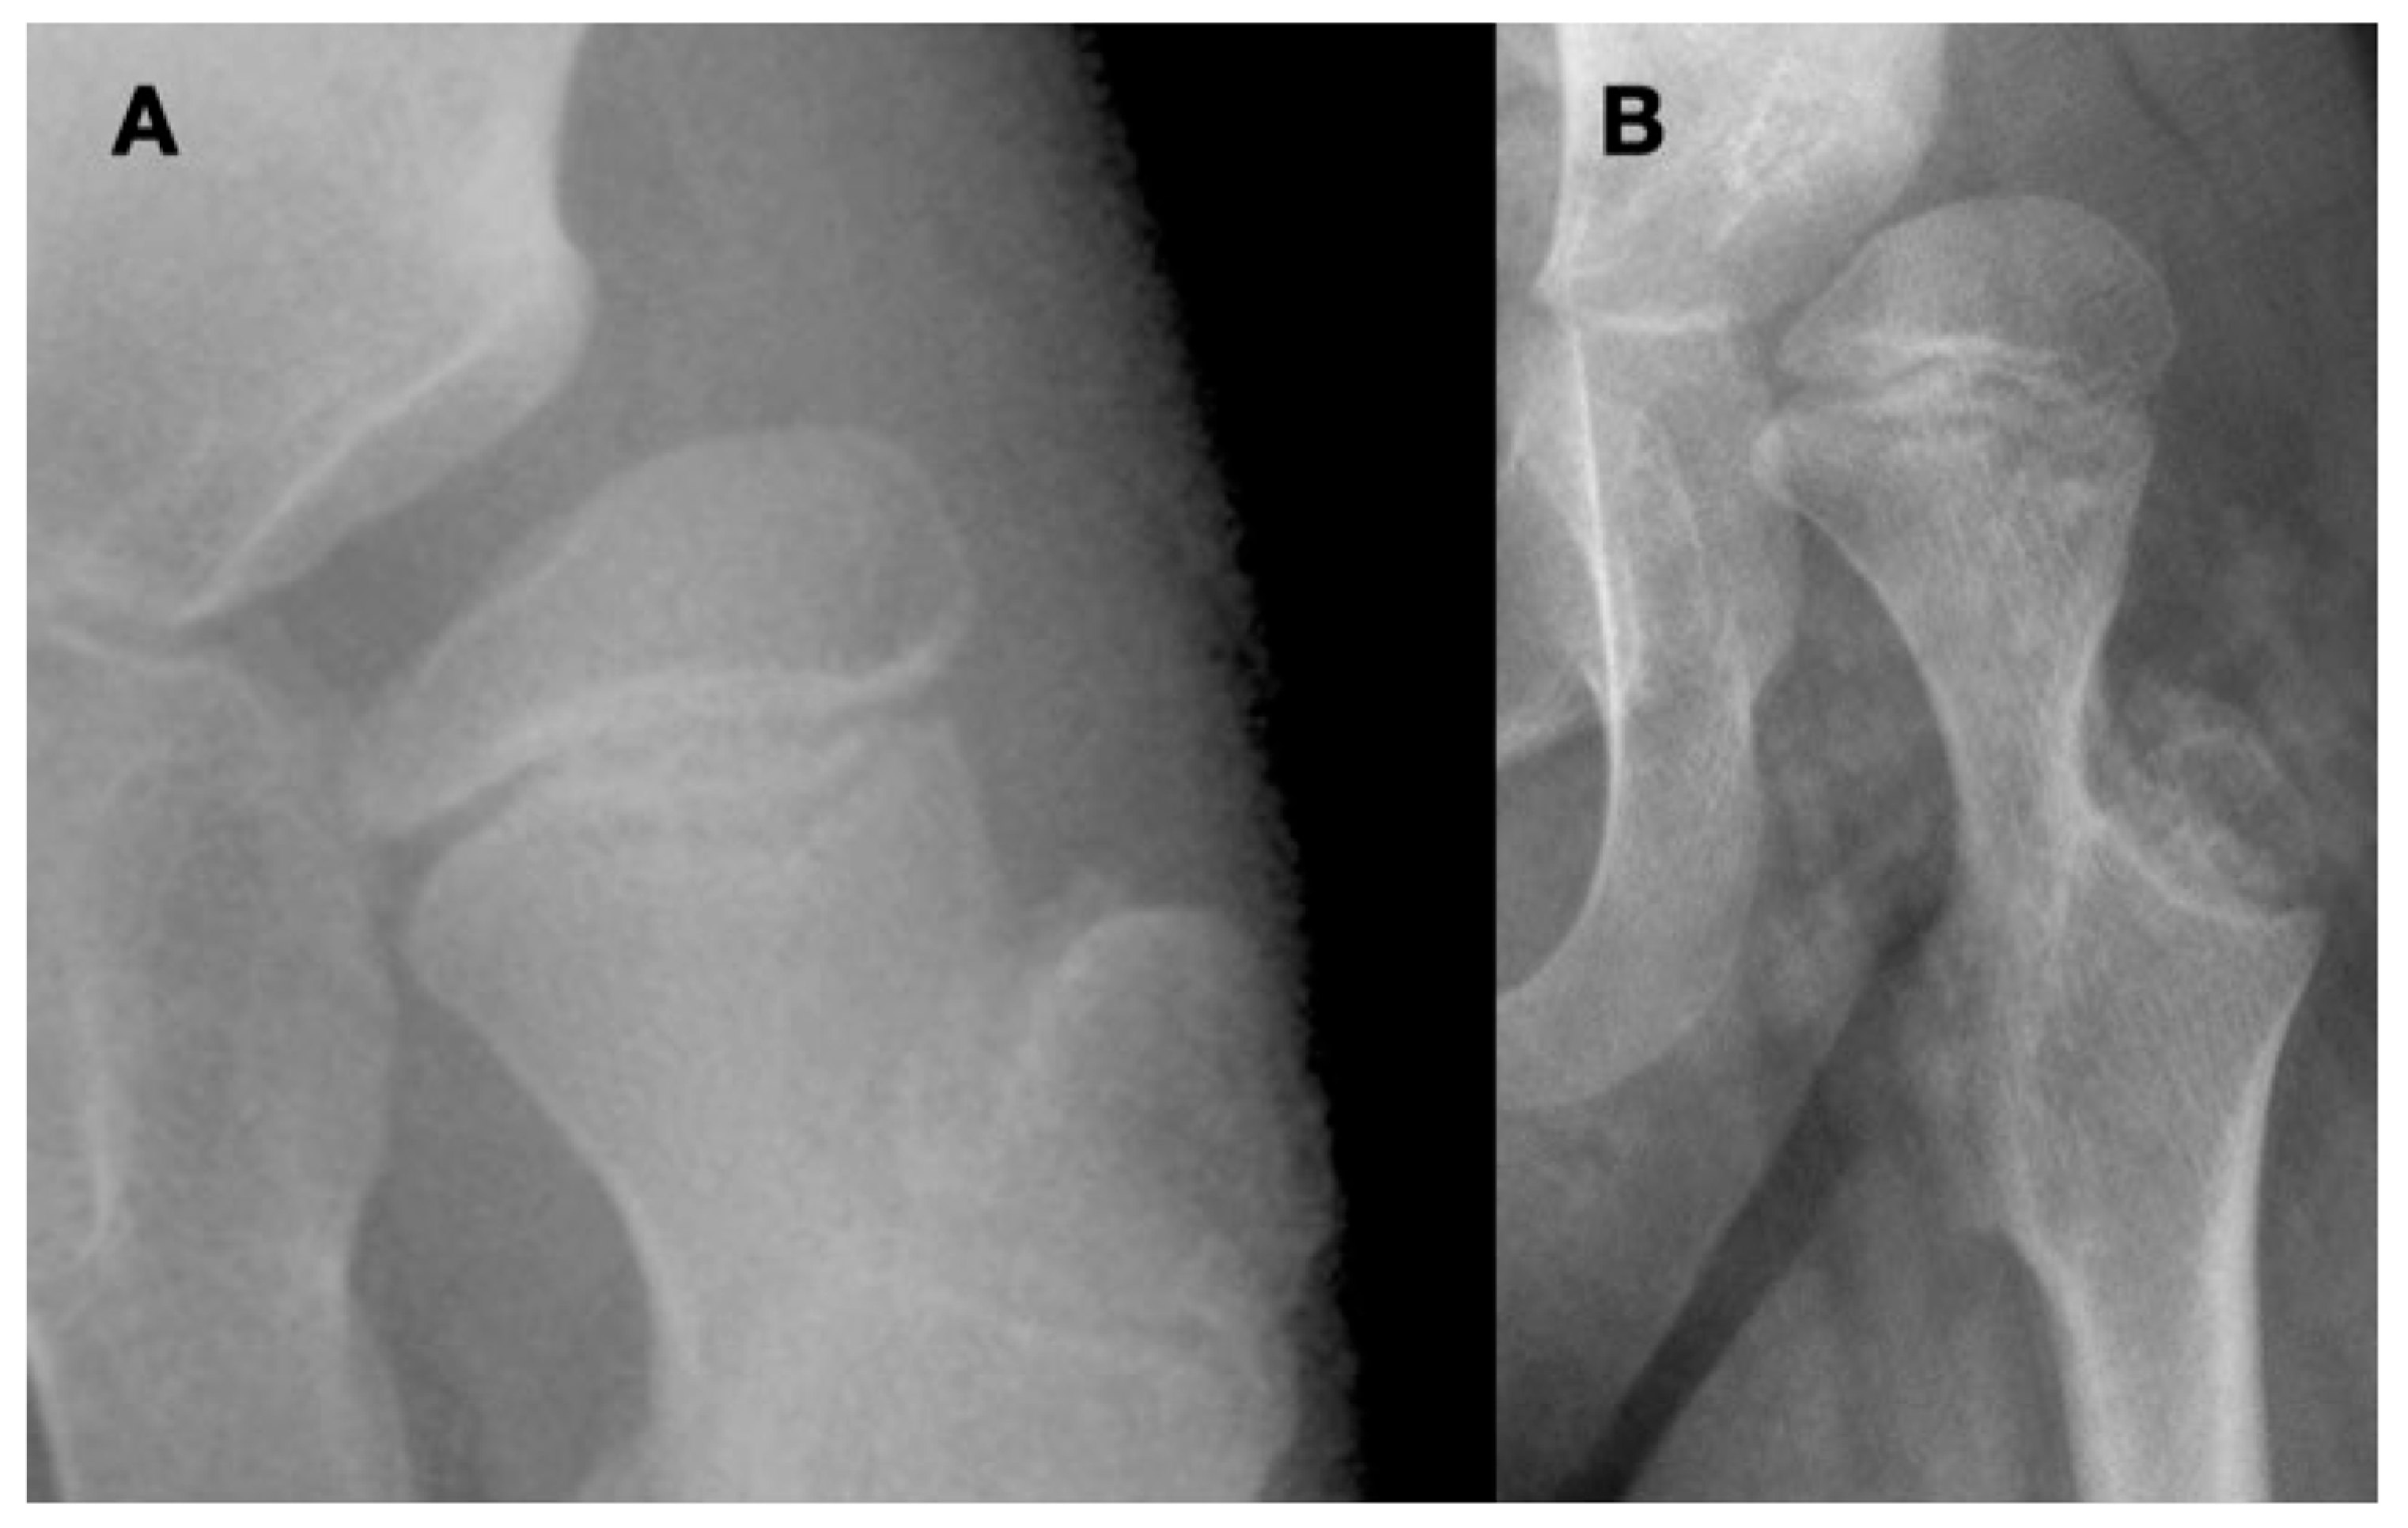

3.4. Femoral Factors Influencing Hip Pathology

3.4.1. Pathologic Role of Femoral Anteversion

3.4.2. Pathologic Role of Coxa Valga and the Impact of its Correction on Spastic Hips